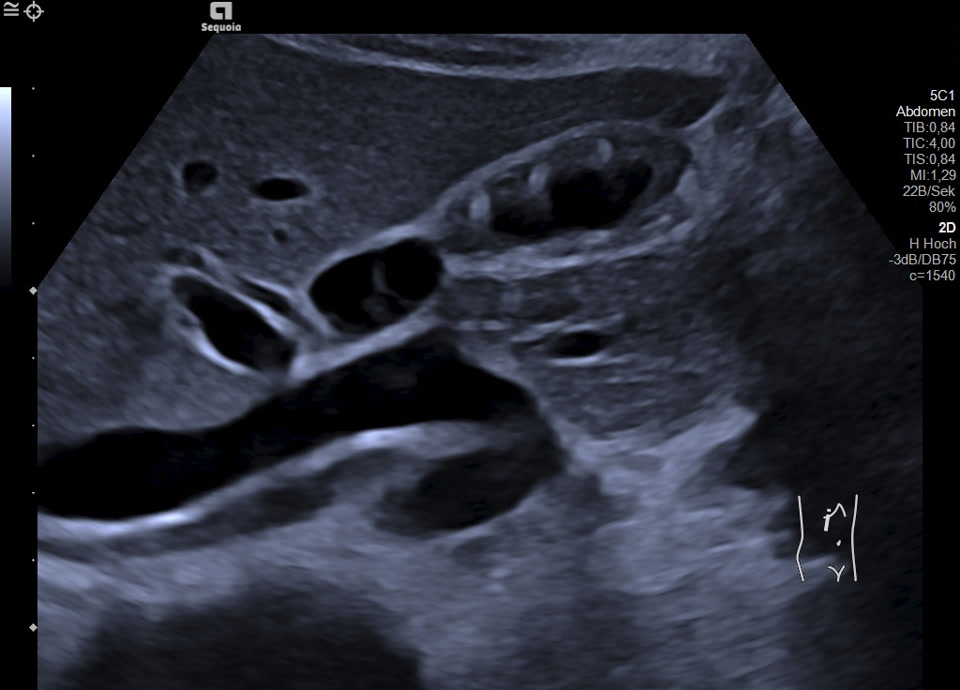

16-jährige Patientin berichtet seit mehreren Monaten über rezidivierende Durchfälle und Bauchschmerzen im Bereich der rechten Colonflexur, zuletzt etwa alle 14 Tage. Vor zwei Monaten wurde sie nach einer besonders starken Episode in die Klinik überwiesen; Labor unauffällig. Zum Zeitpunkt der letzten Untersuchung beschwerdefrei. Sonographisch zeigt sich eine Wandverdickung der Gallenblase mit inhomogener Schichtung bei erhaltener, glatter Innen- und Außenkontur. Betroffen sind vor allem Fundus und Corpus, das Infundibulum erscheint unauffällig. In den verdickten Wandabschnitten finden sich hyperechogene Einzelechos mit Reverberationsartefakten (Kometenschweifartefakte). Zusätzlich zeigen sich in der Hochfrequenzsonografie (Video) echofreie, kleinzystische Areale in der Wand, die den erweiterten Rokitansky-Aschoff Sinus entsprechen. Charakteristischer Befund einer segmentalen Gallenblasenadenomyomatose.